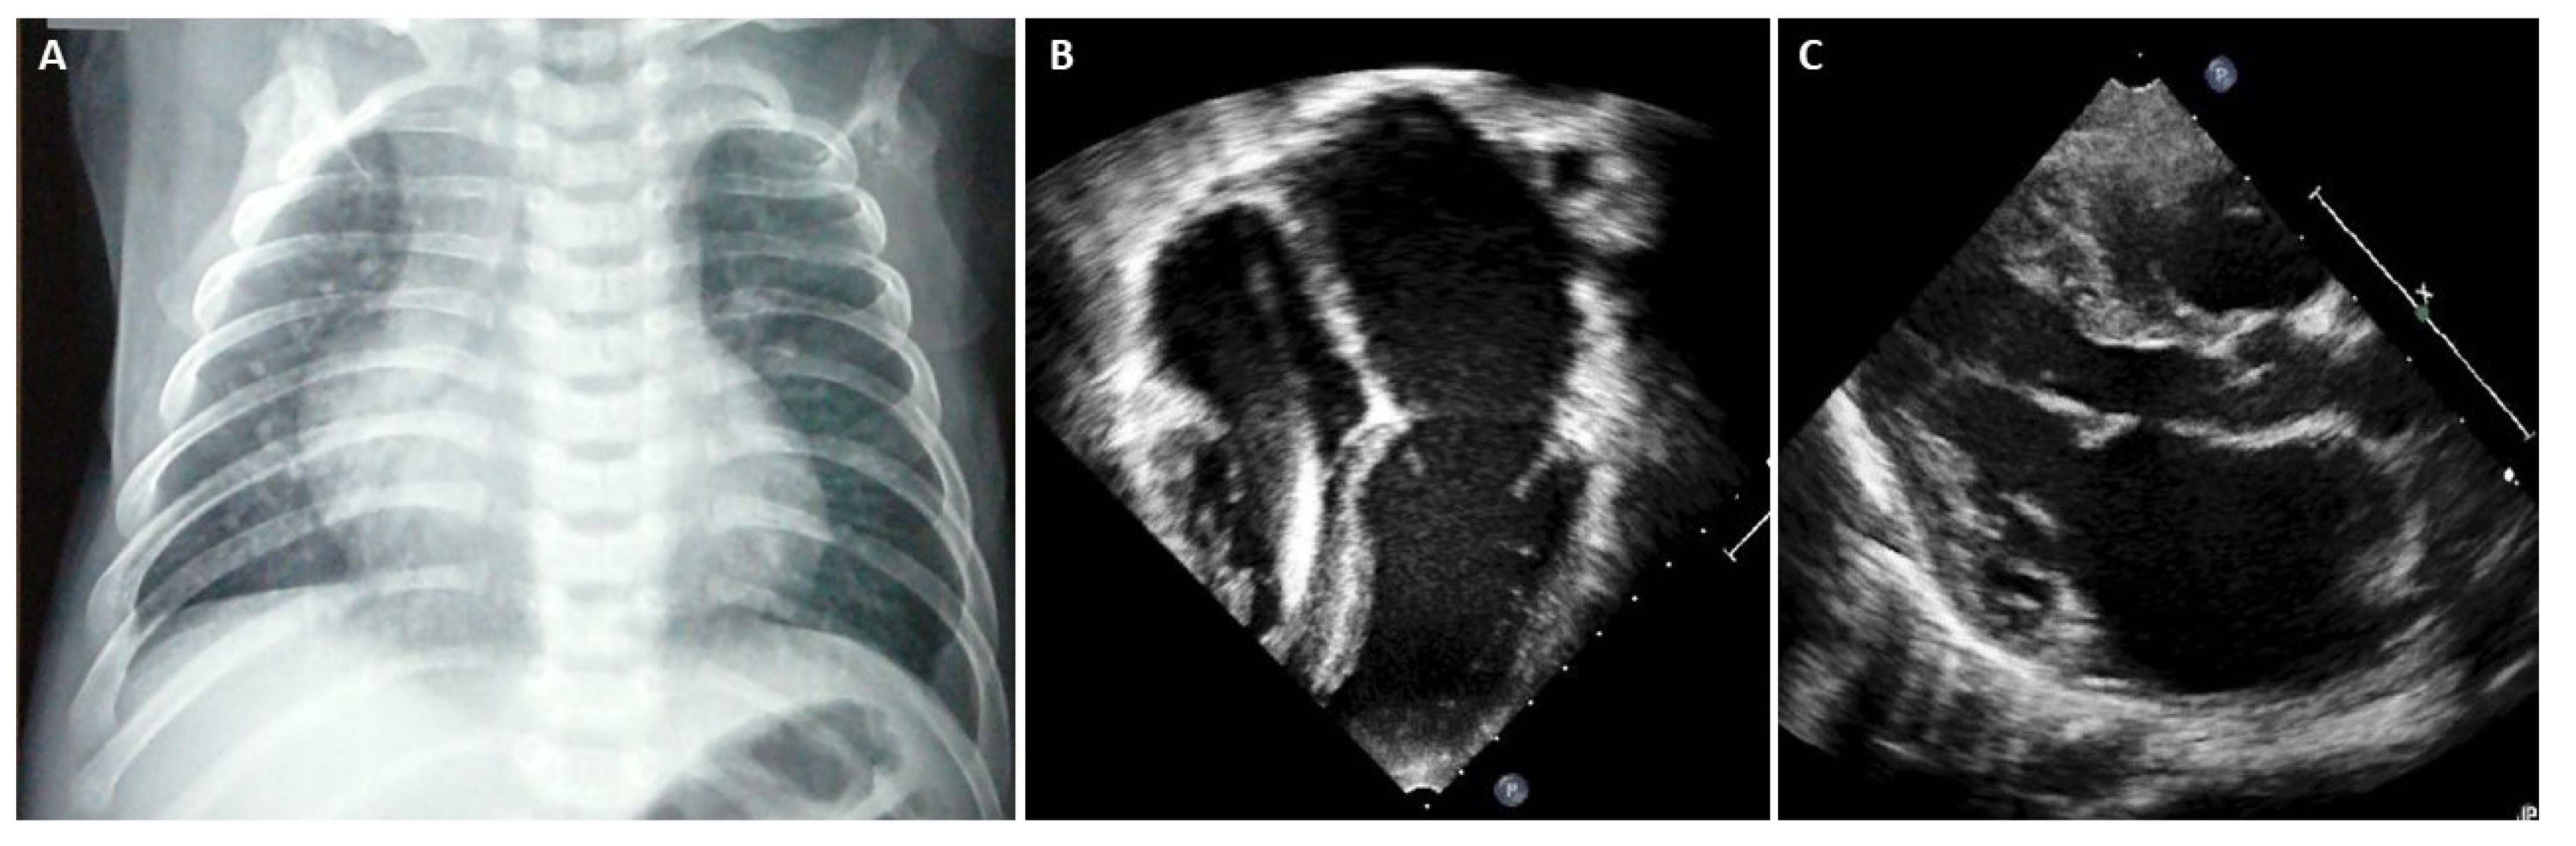

In advanced stages of disease, atrial dilatation is common (Figure 3), pericardial effusion may develop as hemodynamic consequences of increased cardiac filling pressure and Doppler evaluation shows increased early filling velocity (E wave)/atrial filling velocity (A wave) ratio, reduced E wave deceleration time and elevated E/e’ ratio on tissue Doppler.

Figure 3.

(A) Chest X-ray, 8-year-old boy with hypertrophic-restrictive cardiomyopathy and congestive heart failure. (B) Echocardiography apical 4-chambers view, 11-year-old girl with restrictive cardiomyopathy, normal ventricular volumes, preserved ejection fraction and severe atrial dilatation; we can appreciate the presence of an implantable cardiac defibrillator lead. (C) Echocardiography parasternal long axis view, 6-year-old boy with restrictive cardiomyopathy associated to severe left atrial dilatation.

Chest X-ray is often helpful when HF signs are present. In overt RCM phenotype, chest radiography of patients with RCM shows cardiac enlargement due to atrial and pulmonary artery dilatation. In addition, signs of pulmonary congestion and pleural effusion might be present [17].